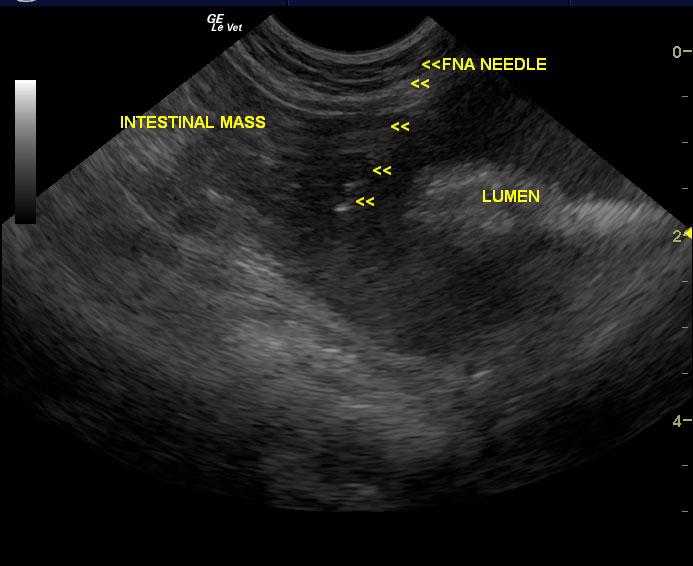

A seven-year-old MN DSH cat was presented with lethargy with the owner reporting that the cat’s behavior and temperament had changed. On urinalysis the urine was straw in color and clear; USPG was inappropriate (1.021), hematuria was present. The urine protein/creatinine ratio was 1.1. Abnormalities on CBC and serum chemistry were anemia, neutrophilia, lymphopenia, monocytosis, hypoproteinemia, and azotemia. Abdominal radiographs revealed an left nephromegaly and a mass effect in the gastrointestinal tract.